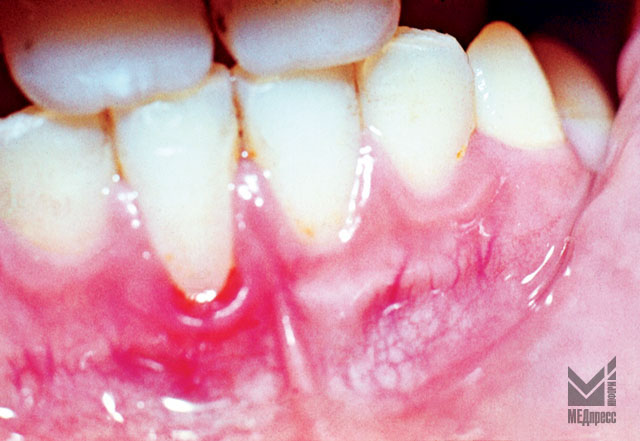

Рис. 6.Перекрестный прикус. Гиперемия и отек десны в области 31, 32, 41, 42 зубов, зубной камень, оголение шеек зубов.